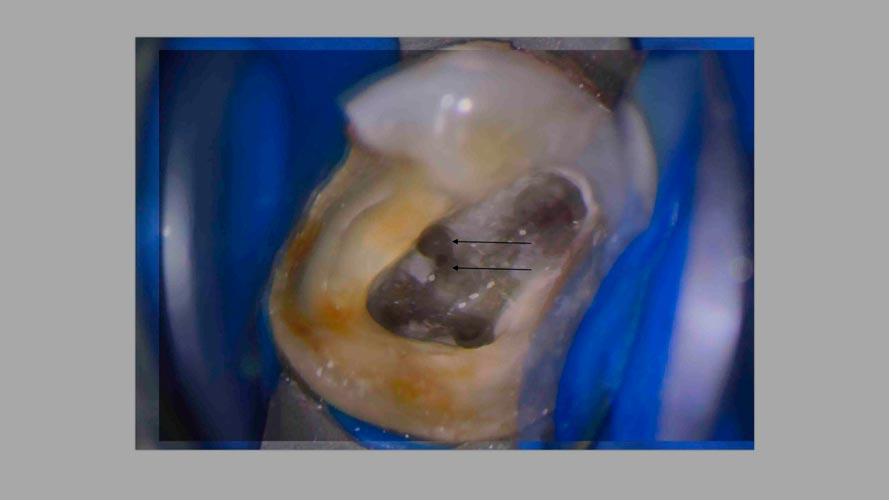

"Підступний" МВ2

Підступний" МВ2

1) Частота поширення та найбільш поширені варіанти анатомії. Особливості анатомії відносно інших каналів.

2) Правила пошуку. Секрети, лайфхаки та як не зробити "діагностичну" перфорацію.

3) Визначення робочої довжини та інструментація в залежності від складності: від скаутингу до повного проходження.

4) Обтурація МВ2 в залежності від складності анатомії, чи завжди це можливо? Що буде, якщо пропустити МВ2?

5) Менеджмент проблем та ускладнень на різних етапах. Розбір клінічних кейсів.